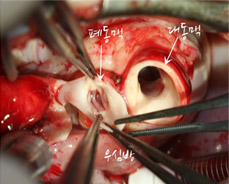

[사진1] 대동맥 뒤에 위치한 폐동맥이 관찰됨. 폐동맥 자체가 작고 이엽 판막임. 대혈관치환술 하기에는 폐동맥 판막의 모양이 좋지 않음.

[사진2] 폐동맥근과 대동맥근을 한꺼번에 떼어낸 뒤 360도 회전해서 다시 연결한다.

[사진3] 심실에서 분리한 폐동맥과 대동맥근